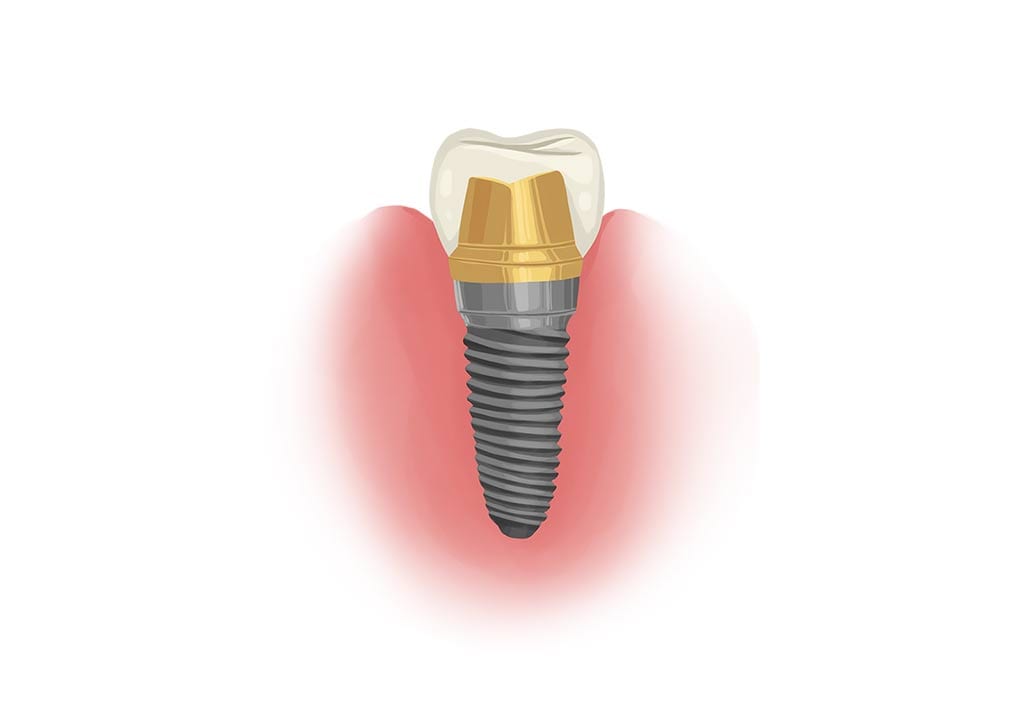

Dental implants are a long-term solution to missing teeth. When an adult tooth is lost, the area of jawbone that held the tooth begins to deteriorate. In preparation for a dental implant, a bone grafting procedure is typically done first. If all goes well, the bone graft and implant can last for a lifetime.

Dental implants are permanently situated in your mouth, so unlike dentures, they stay in place just like your own teeth. The root of the tooth is replaced by a screw, which becomes the artificial root. The screw sits in the jawbone and fuses with your jawbone, helped by the bone graft procedure.

The bottom line is these factors all influence how your body heals. Receiving dental implants first relies on your body integrating your bone grafts, and then on your jaw being strong enough to support the titanium implant screw for each implant.

Another reason that tooth grinding hinders success is that movement slows down the osseointegration. This is the process of the bone fusing with the implant and forming a permanent attachment.